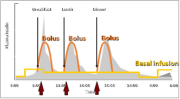

| 05:22, 14 באוגוסט 2023 | הזלפת אינסולין5.png (קובץ) |  |

144 קילו־בייטים | Motyk | 1 | |

| 05:20, 14 באוגוסט 2023 | הזלפת אינסולין1.png (קובץ) |  |

316 קילו־בייטים | Motyk | 1 | |